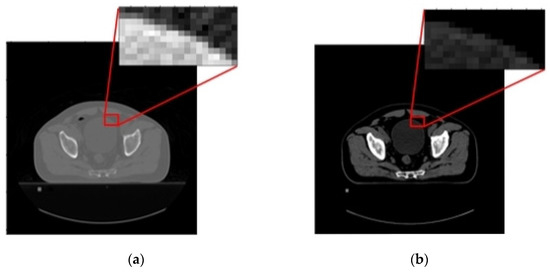

3.2. Contrast Enhancement and Femur Cropping